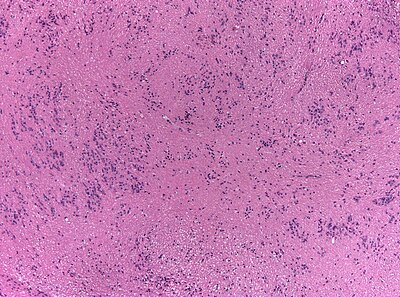

4

Diagnosis?

Oligodendroglioma1 high mag.jpg

Pilocytic astrocytoma

Diffuse Astrocytoma

Pleomorphic xanthoastrocytoma

Subependymal giant cell astrocytoma

Oligodendroglioma

Glioblastoma, classic

Glioblastoma, epitheloid

Giant cell glioblastoma

Gliosarcoma

Ependymoma

Subependymoma

Myxopapillary ependymoma

Ganglioglioma

Choroid plexus papilloma

Angiocentric glioma

Dysembryoplastic neuroepithelial tumour

Neurocytoma

Paraganglioma

Pineocytoma

Papillary glioneuronal tumour

Medulloblastoma

CNS PNET